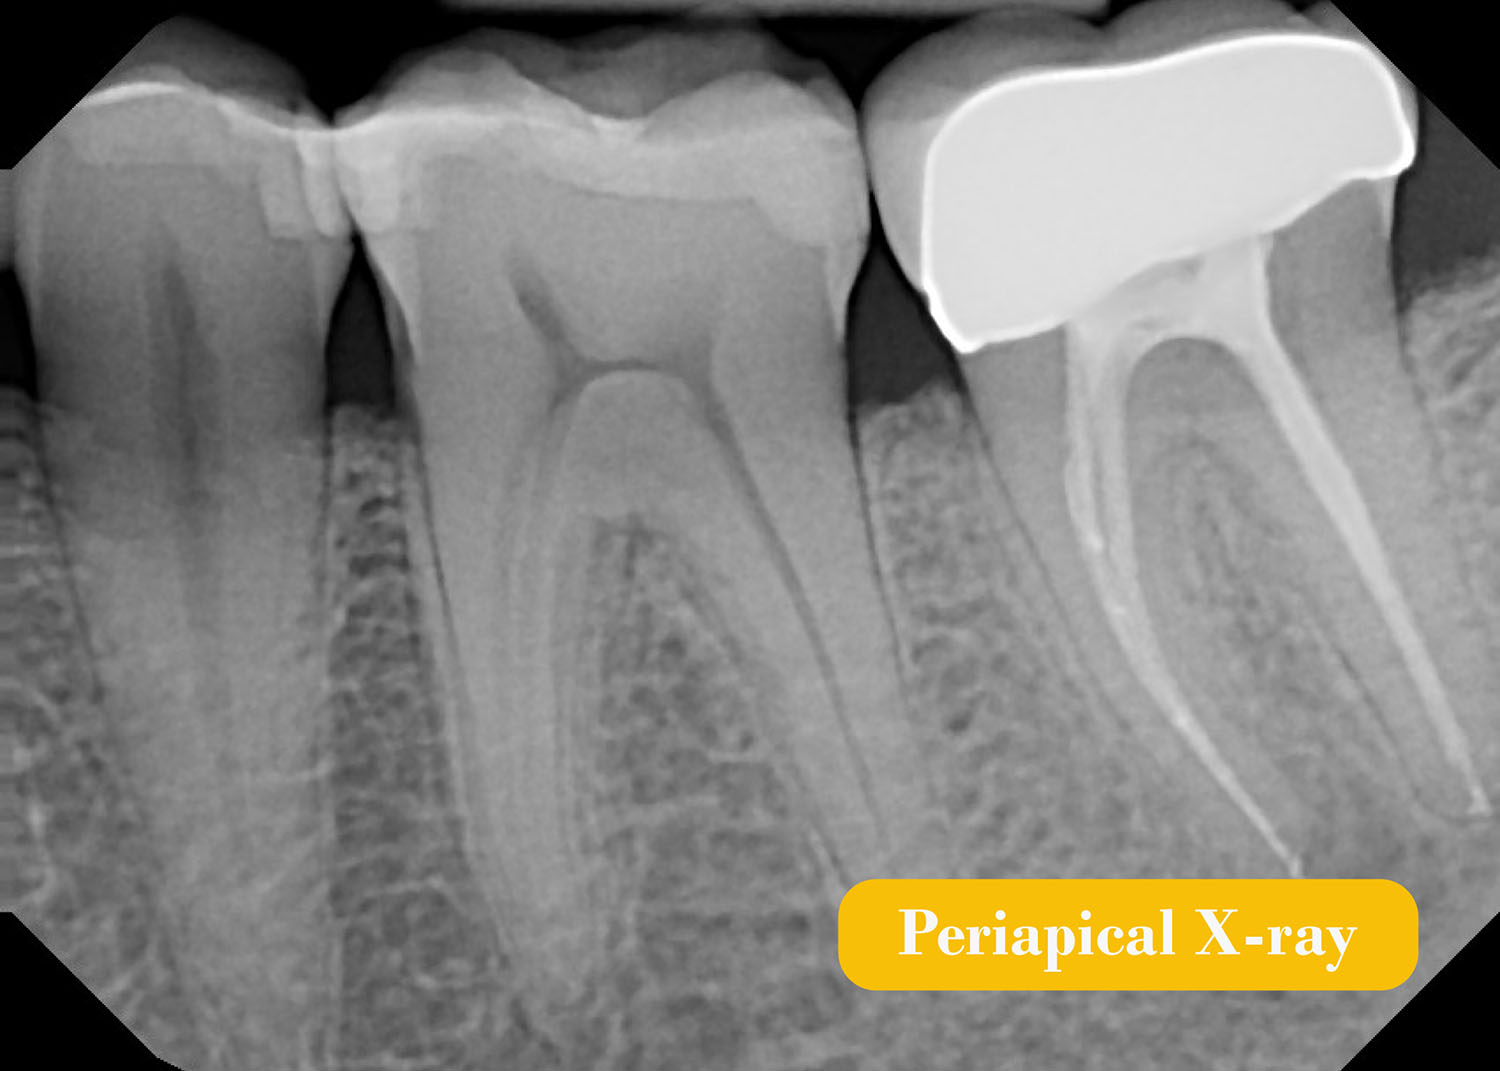

7 Periapical radiography Pocket Dentistry Dental X Rays Technique The bisecting angle technique is accomplished by placing the receptor as close to the tooth as possible. From detecting cavities in their nascent stages to aiding in complex orthodontic procedures, these imaging techniques ensure that dental care is both thorough and precise. Dental X Rays Technique.